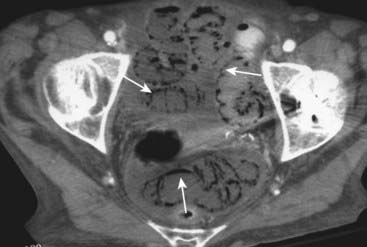

Figure 15-14 Necrosis of bowel from mesenteric ischemia.

Axial CT image of the pelvis demonstrates multiple loops of bowel with punctate collections of air throughout their walls consistent with pneumatosis (solid white arrows). The patient had widespread ischemia of bowel from mesenteric vascular disease. Pneumatosis that results from bowel necrosis is an ominous sign.